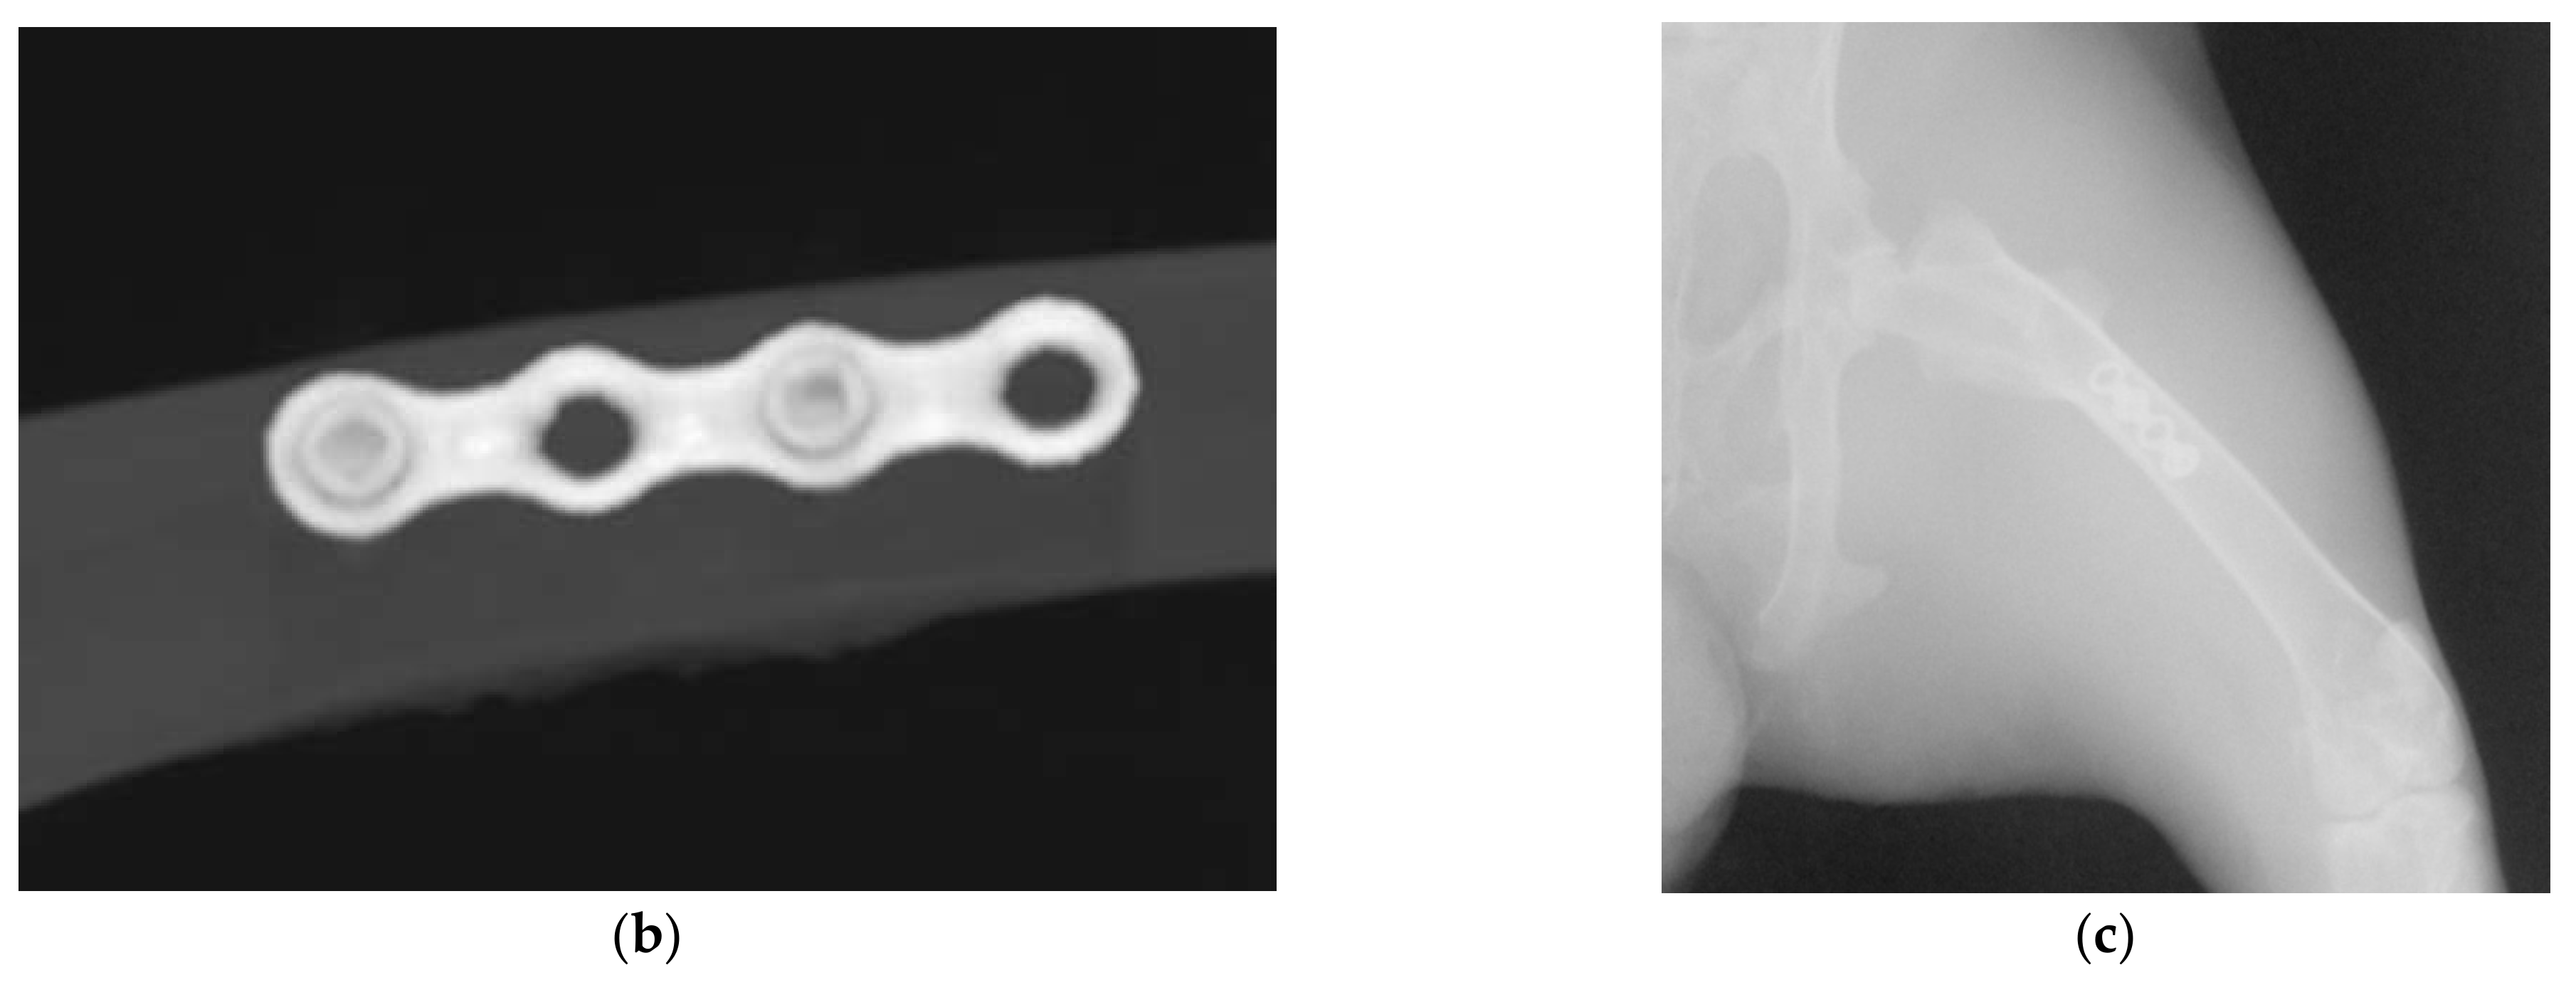

4.1. Titanium Implants

4.1.1. Milled-Titanium Implant

4.1.2. Sintered (DMLS)-Titanium Implant

4.2.2. Implantation of Titanium Plates and Screws